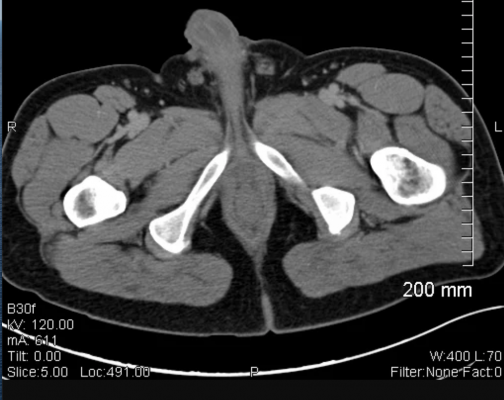

In order to be eligible for NRG-RTOG 0526, prostate cancer patients needed to have low or intermediate risk prostate cancer prior to EBRT in addition to having a proven LR thirty or more months following their EBRT. 92 patients were analyzed for the study and followed for a minimum of 5 years after their salvage brachytherapy. Participants on NRG-RTOG 0526 received a minimum dose of 140 Gy with I-125 or 120 G with Pd-103. Researchers followed clinical outcomes at 5 year or greater including objectives such as disease-specific survival, overall survival, time to biochemical failure, and patterns of recurrence.

As initially reported, 14% of participants experienced late Grade 3 gastrointestinal and genitourinary AEs at a median follow up of 6.9 years. The median prior EBRT dose was 74 Gy and the median interval since EBRT was received was 85 months. Androgen deprivation therapy was combined with salvage BT in only 16% of cases. The 5-year freedom from biochemical failure rate was 68%, which is comparable to other salvage modalities. At 10 years, the biochemical failure rate was 54% (95% CI: 43-66). Disease-free survival at 5 years was 61% but fell to 33% at 10 years. Nineteen patients died. Four patients had local recurrence (5% at 10 years), and 14 had distant failure with a 10-year rate of 19% (95% CI:10-29). None of the clinical or treatment factors was significantly associated with participants' overall survival, disease-free survival, or local, distant, or biochemical failure.